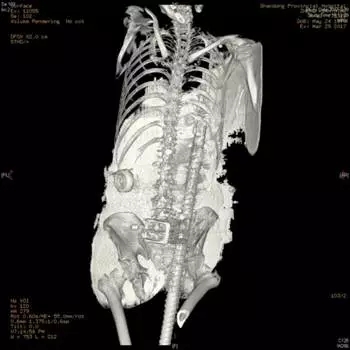

三维CT重建可见钢筋贯穿胸、腹、盆腔

3月29日晚,一例严重贯通伤患者被紧急送入我院东院急救中心。患者不慎从高处坠落,钢筋从会阴部刺入,经过盆腔、腹腔,从胸部后方穿出,情况十分危急。

医院骨科主任周东生,东院急诊外科主任医师孙宝友,骨科主任医师李连欣、副主任医师张鹏等在各科专家配合下实施手术。因钢筋贯穿胸腔、腹腔、盆腔,专家们分别从三个部位进行切开,让钢筋充分显露,随后在清楚直视下将其缓慢抽出。次日凌晨3:30分左右,1米多长、直径2.5公分的钢筋被完整取出。医护人员随即对伤者进行清创探查和伤口修复,手术顺利结束,伤者被送往重症监护室接收后续治疗。